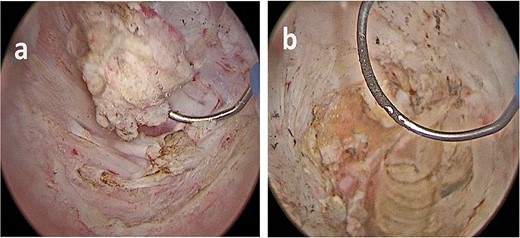

A successful cognitive biopsy of the prostate and left seminal vesicle was performed, immediately after the trans urethral resection of the right bladder lesion. Under general anesthesia, the patient was placed in a dorsal lithotomy position. We started by identifying the cognitive target on the left prostate lobe and proceeded with the biopsy (a random biopsy was also performed). At the urethrocystoscopy, there were no visible lesions in the bladder. With the suprapubic ultrasound, we identified the lesion and we marked it with the Collings loop, and we completed the excision with the standard bipolar loop (Figs 2 and 3).

(a) Endoscopic vision during resection. (b) Endoscopic and ultrasound contemporary vision of the lesion.